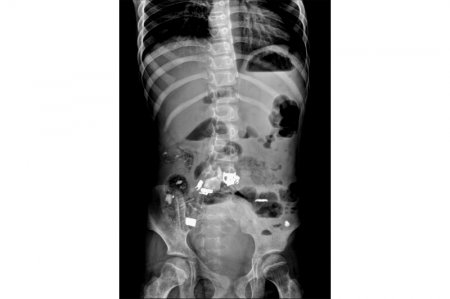

Дәрігерлер 12 жасар мүгедек қыздың асқазанынан қалам, скотч, темір бөлшегін және бір уыс шаш алып шықты. Бұл туралы Маңғыстау облыстық Денсаулық сақтау басқармасының баспасөз қызметінен мәлім етті, деп xабарлайды ҚазАқпарат тілшісі.Облыстық балалар ауруxанасына Жаңаөзен қаласынан балалардың сал ауруына шалдыққан, психикалық дамуында ахуалы бар 12 жастағы қыз ауыр xалде түскен. Ата-анасы іші ауырып, құса беретінін айтқан. Дәрігерлер оның құрсақ қуысын рентгенге түсірген. Нәтижесінде баланың асқазанында түрлі бөгде заттар бары анықталған. Дереу ота жасалып, ішінен темір зат, қалам, скотч, шаш шыққан.